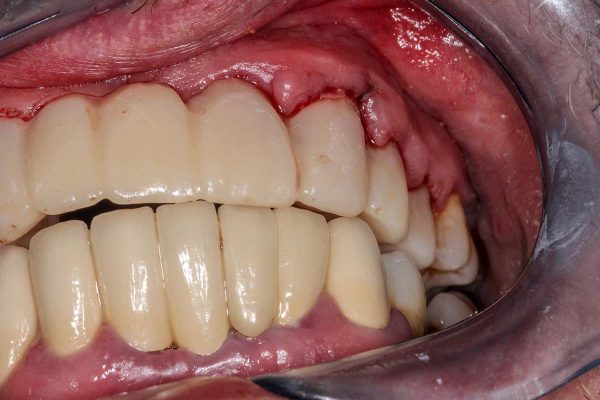

Gingival Hyperplasia

Gingival hyperplasia is caused by excessive tissue growing around the teeth, usually caused by a decreased immune system, which is common in cancer patients receiving chemotherapy and radiation therapy. While gingival hyperplasia is not a rare side effect of chemotherapy, it is one of the most commonly reported side effects in chemo patients. This condition is often harmless but can also cause discomfort or pain for the patient. Gingival hyperplasia is reversible with support from a doctor at Holistic dentistry.